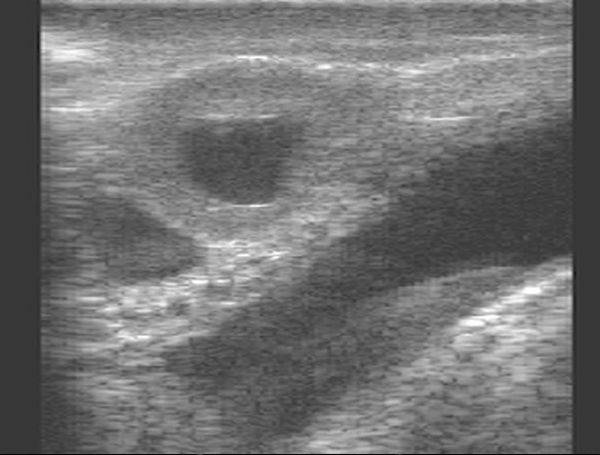

Гистологические изображения фолликулярной кисты яичника